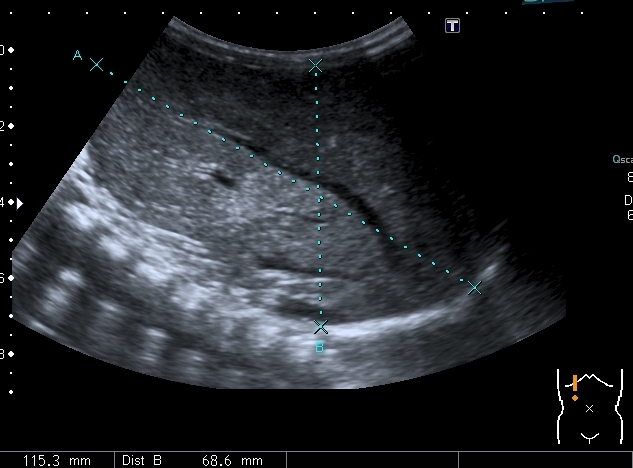

При УЗИ: печень резко увеличена, больше за счёт левой доли

Левая доля

Левая доля прилежит к селезёнке, оттесняет её вниз и дорзально

Паренхима печени -гиперэхогенная , неоднородная, практически полностью замещена нодулярными образованиями, некоторые из них с "гало" и кальцификацией